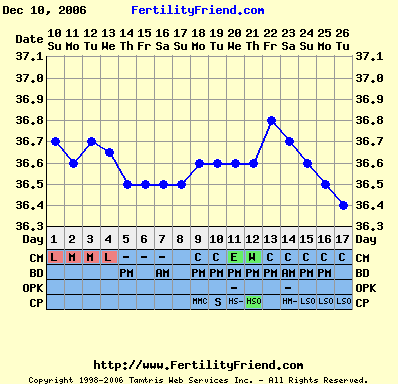

Nem tudom, hogy ez normális-e, miközben minden hormonom rendben, és a hőgörbe mutat pé-t. Meg van pozitív LH tesztem is...

Gaby: a Te görbéd elég cikkcakkos, szerintem később pé-zel...Végülis hathatott a párodnál már a gyógyszer, ha nem is drasztikusan, de már jobbak lehetnek az eredményei...